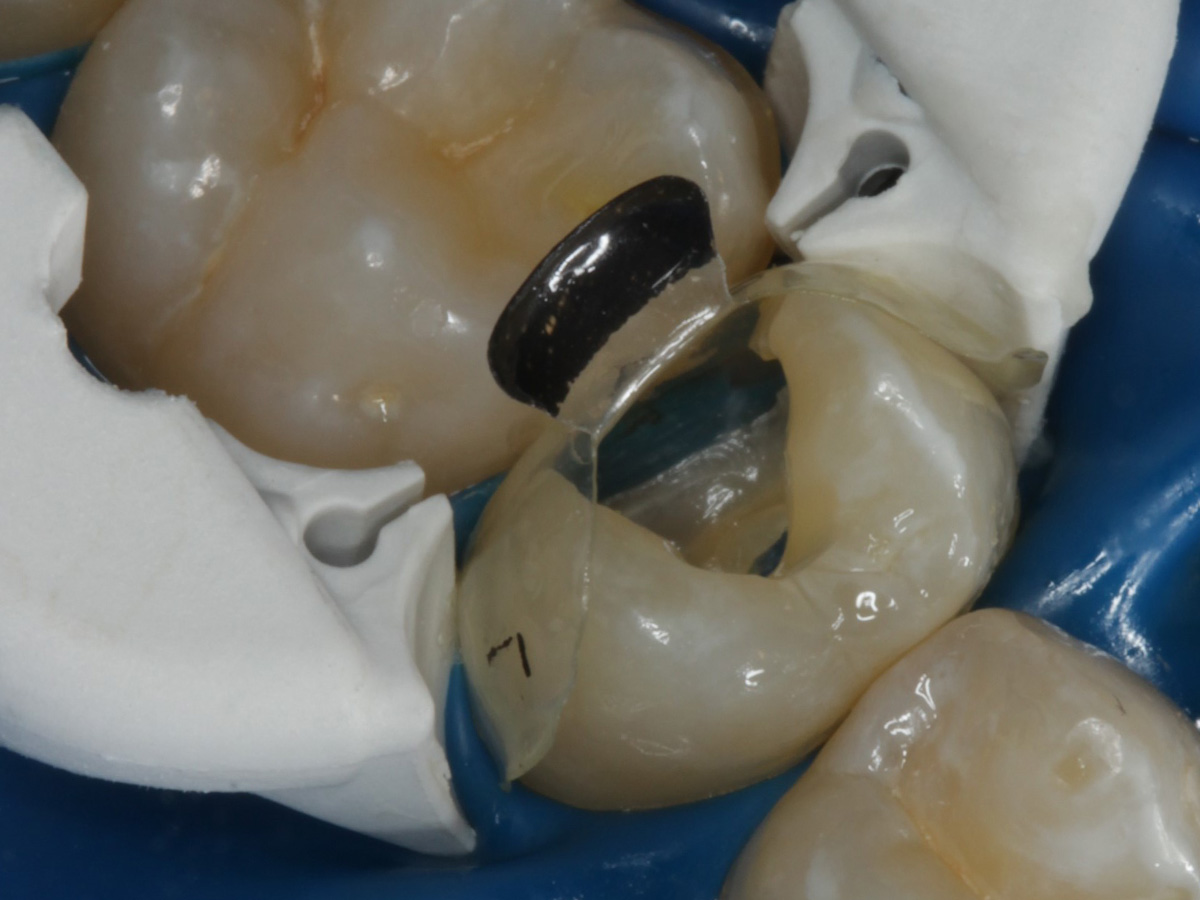

Abbildung 4

Schutz des Nachbarzahnes und des Kofferdams mit wiederverwandter Bioclear Biofit Matrize (gereinigt und sterilisiert)